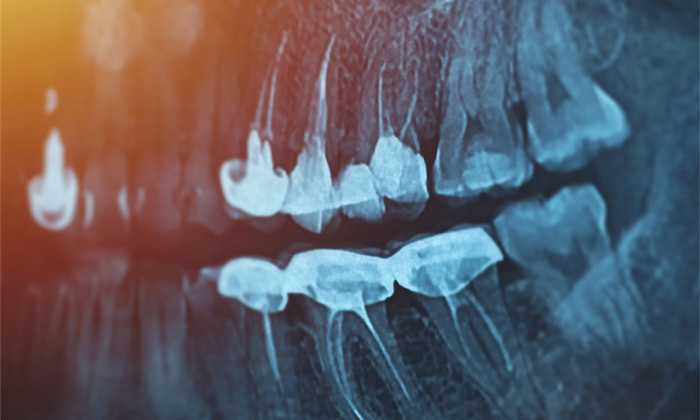

レントゲン撮影(CT撮影)を行い、画像を見ながら抜歯の手技、抜歯にかかる時間などの説明をさせていただきます。抜歯に関するご質問がございましたら、お気軽にお声がけください。